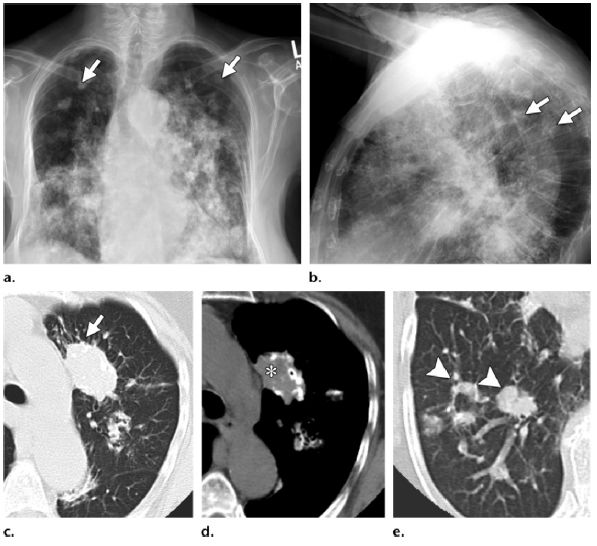

图3 (a,b)患者,女,82岁,患有边缘区淋巴瘤

,胸部X线示其所致的淀粉样变性肺实质结节改变。除了纵隔淋巴结钙化,多发肺结节钙化(箭头示)发生在双侧。(c-e)该患者CT示肺内结节部分钙化(图d*)。这个结节部分边缘可见毛刺(图c箭头)。右肺可见一些部分钙化或无钙化结节(图e箭头),许多边缘可见毛刺。鉴别诊断包括尘肺、肉芽肿性感染及结节病

。经皮右下肺穿刺为肺实质性淀粉样变性。